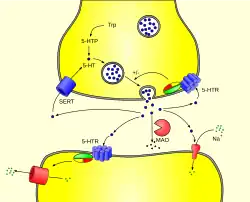

Abbau

Das Serotonin der Nervenzellen wird nach seiner Freisetzung in den synaptischen Spalt aktiv mit Hilfe des Serotonin-Transporters (SERT), eines Transportproteins, rückresorbiert und wiederverwertet. Das aus den enterochromaffinen Zellen produzierte Serotonin wird rasch nach seiner Freisetzung über das gleiche Transportprotein in den Epithelzellen der Darmschleimhaut und in den Thrombozyten gebunden. Der Abbau von Serotonin erfolgt vorrangig über das Enzym Monoaminooxidase (MAO) vom Typ A und in einem deutlich geringeren Maß über MAO Typ B. Das Produkt 5-Hydroxyindolylacetaldehyd wird von der Aldehyd-Dehydrogenase weiter zu 5-Hydroxyindolylessigsäure (5-HIES) abgebaut. 5-Hydroxyindolylessigsäure, die im Urin nachgewiesen werden kann, ist das Hauptausscheidungsprodukt von Serotonin.

Zentralnervensystem

Serotonin, das sich im Zentralnervensystem in den Zellkörpern, den Somata serotoninerger Nervenbahnen in den Raphe-Kernen befindet, deren Axone in alle Teile des Gehirns ausstrahlen, beeinflusst unmittelbar oder mittelbar fast alle Gehirnfunktionen. Zu den wichtigsten Funktionen des Serotonins im Gehirn, das die Blut-Hirn-Schranke nicht überwinden kann und daher vor Ort gebildet werden muss, zählen

Serotonin fungiert dabei einerseits als Neurotransmitter im synaptischen Spalt, andererseits wird es diffus über freie Nervenendungen ausgeschüttet und wirkt als Neuromodulator.[59]